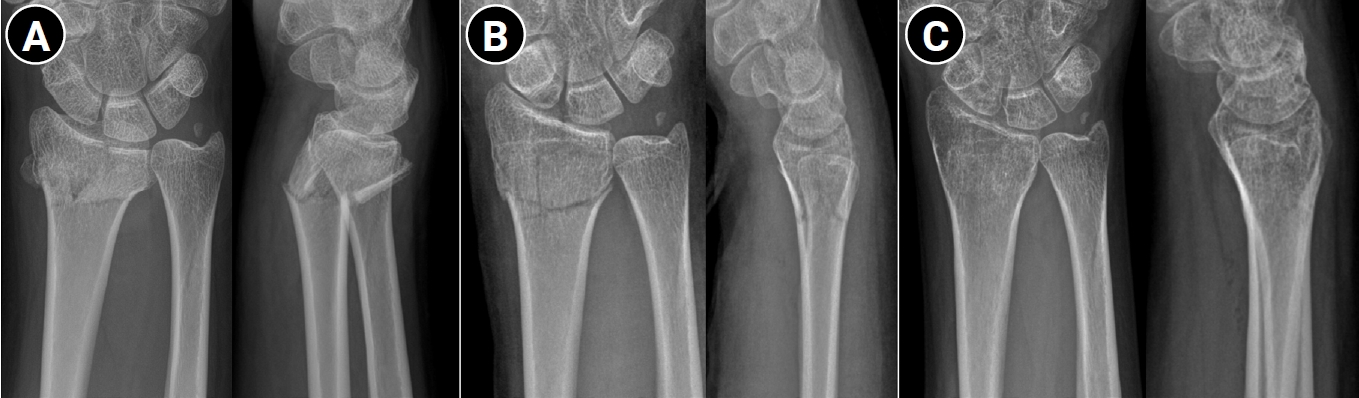

Fig. 2.

Outcome of conservative treatment in an older patient with a displaced distal radius fracture. Radiographs of a 71-year-old female patient. (A) Wrist anteroposterior and lateral radiographs obtained after initial reduction, demonstrating distal radius and ulnar styloid fractures with intraarticular comminution of the left wrist. Volar tilt and radial length were well restored after reduction. (B) Wrist radiograph obtained 1 year after trauma, showing radial shortening and dorsal tilt of the distal radius. (C) Range of motion of the left wrist was slightly decreased compared with the right side; however, the patient was able to perform daily activities without pain at one year after trauma.

Rather than applying strict radiographic criteria uniformly across all patients, more stringent criteria may be appropriate for younger, active individuals, while more flexible thresholds may be suitable for elderly patients with comorbidities or low functional demands. In particular, several studies have reported that unsatisfactory radiographic results do not always correlate with unsatisfactory functional outcomes in elderly patients [29,30]. Kyung et al. [31] reported that dorsal metaphyseal comminution did not significantly affect radiographic or functional outcomes in patients treated nonoperatively. Kim et al. [32] compared elderly patients (≥65 years) treated nonoperatively versus operatively for unstable distal radius fractures and found that although radial shortening was more pronounced in the nonoperative group, functional evaluation and wrist range of motion did not differ significantly between groups. A recent randomized trial of intraarticular fractures found that intraarticular incongruity did not significantly affect functional outcomes, even though radiographic differences were present (Fig. 2) [16]. These findings support the premise that in elderly patients with lower functional demands, nonoperative treatment can achieve satisfactory outcomes even when anatomical restoration is not perfect.